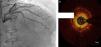

Regarding lesion type, 14 had CAV1 (38%), 12 had CAV2 (35%) and nine had CAV3 lesions (24%). During the follow-up period, six (16%) patients showed disease progression: four patients first classified with CAV1 showed progression to CAV2, and two CAV2 patients progressed to CAV3. The other patients presented a stable CAV course during follow-up. Percutaneous coronary intervention (PCI) was performed in 18 (49%) patients in the CAV+ group, in lesions classified as CAV2 and CAV3 (only focal stenosis or critical subocclusive lesions amenable to PCI). Seventeen drug-eluting stents (DES) with everolimus, sirolimus or zotarolimus, and one bioresorbable vascular scaffold (BVS), were implanted in 10 of these patients. The patient treated with BVS presented with restenosis ten months later, as illustrated in Figures 1-3, highlighting the safety issues related to these devices, which are no longer in use (Figure 4).

Patients with CAV are usually asymptomatic because of allograft denervation, and so ICA is the standard diagnostic technique.10 However, its sensitivity is limited by the diffuse nature of CAV, especially during the first year post-OHT.10,11 Intracoronary imaging techniques such as intravascular ultrasound (IVUS) and optical coherence tomography (OCT) are therefore of growing importance in the diagnosis of CAV.10,19–21

Using ICA for CAV diagnosis is in agreement with recent ISHLT recommendations, but it has limited ability to detect the early stages of CAV.22 Other imaging techniques, including IVUS and OCT,20,21 may have greater sensitivity for CAV diagnosis.38 The inclusion of these techniques in follow-up programs could lead to earlier detection of abnormalities after OHT and provide more accurate identification of CAV predictors, although this would significantly increase the program cost and the time taken for each invasive exam.